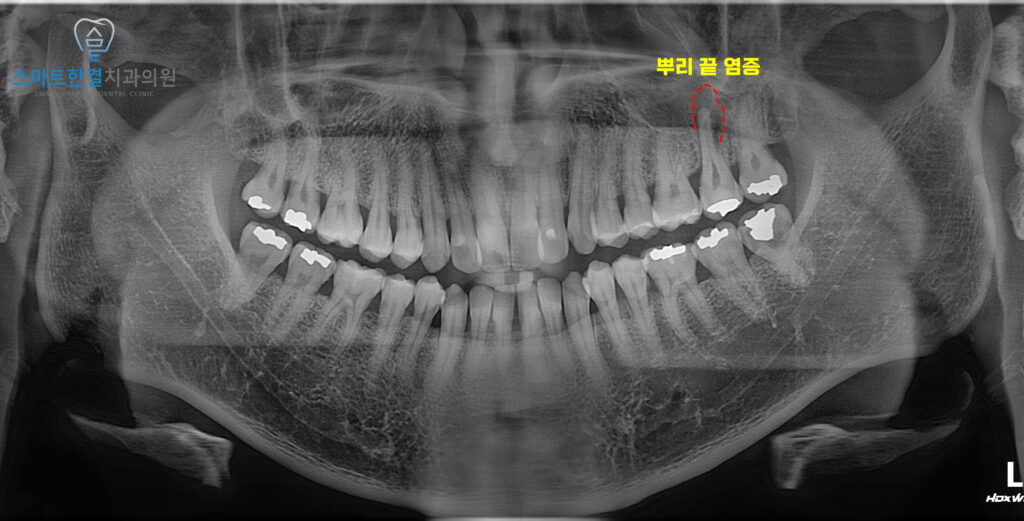

25.01

파노라마 상에서

치아 뿌리 끝으로 염증이 잡혀있는 모습을

확인할 수 있었어요.

이는 치아 내부 감염이

치근단까지 진행된 상태로,

주변 골 조직의 손상까지

동반된 것으로 판단할 수 있었는데요.